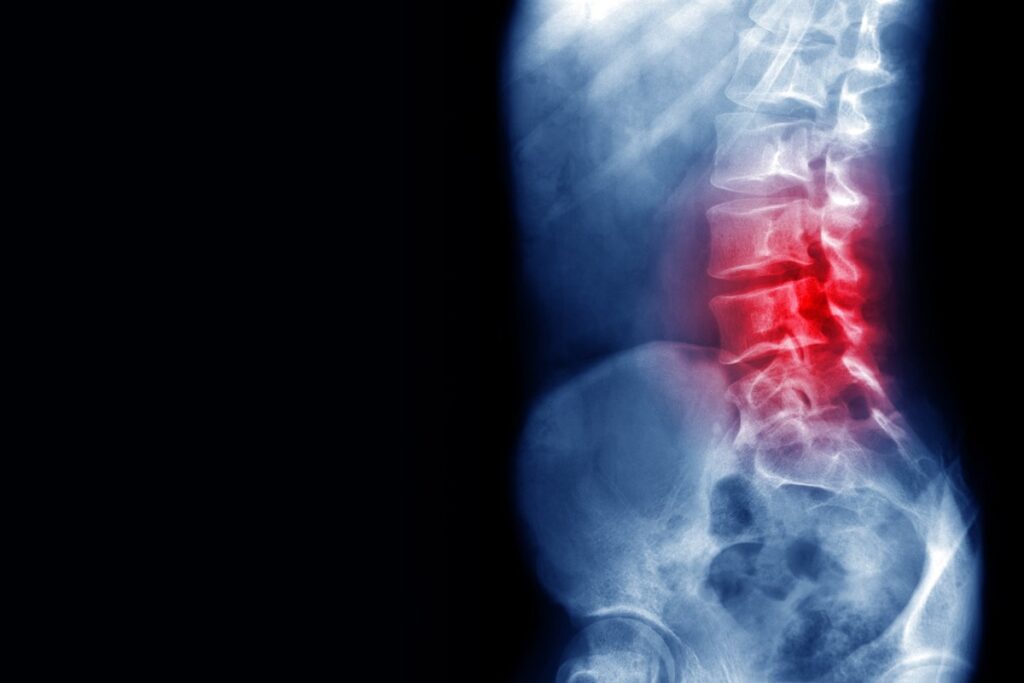

Quando aplicada diretamente na medula espinhal lesionada, a substância criada a partir de uma proteína natural do corpo, chamada laminina, ajuda os nervos a se reorganizarem e voltarem a se comunicar.